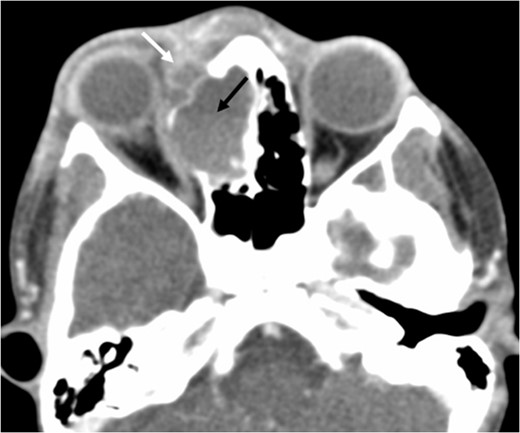

A 6-year-old boy with a background of asthma presented to a tertiary paediatric unit in May 2016 with a 3-day history of right eye pain, proptosis and erythema under the care of the ENT team. A provisional diagnosis of a periorbital cellulitis was made secondary to ethmoid sinusitis and management with intravenous antibiotics (ceftriaxone), intranasal steroids, saline douches and topical oxyxlometazoline was initiated. Ophthalmological assessment demonstrated normal colour vision, acuity and light reflexes bilaterally but also proptosis-related ophthalmoplegia. Computed tomography (CT) imaging of the orbits and paranasal sinuses demonstrated complete opacification of the right-sided paranasal sinuses and compromise of the right frontal and ostiomeatal unit. In addition there was an expansile abnormality centred on the ethmoidal labyrinth with bony remodelling of the lamina papyracea and a subperiosteal collection adjacent to the medial orbital wall (Figs 1 and 2). The most likely diagnosis was felt to be an infective process with mucopyocele formation complicated by a subperisoteal post-septal collection. An MRI scan with gadolinium of the orbits and sinuses confirmed the unilateral pattern of sinus opacification within the right frontal, ethmoids and maxillary sinus. The lesion demonstrated multiple fluid–fluid levels and peripheral enhancement (Figs 3 and 4). The patient was treated by endoscopic drainage of the lesion, which revealed only blood. He initially had some improvement of his proptosis but recurred within a few days and so further, more extensive endoscopic debridement was performed.

Axial non-contrast CT demonstrating an expansile lesion centred on the right-sided ethmoidal labyrinth (long white arrow) with remodelling of the lamina papyracea (short white arrows).